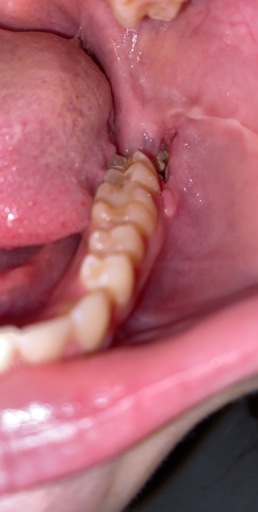

Jaw Bone Showing After Wisdom Tooth Extraction

Hello! One week ago I have two wisdom teeth removed, both being on the same side of my mouth. I had an infection on my bottom wisdom tooth and was given antibiotics prior to the extraction. Since the surgery, I have had dull pain from that one...